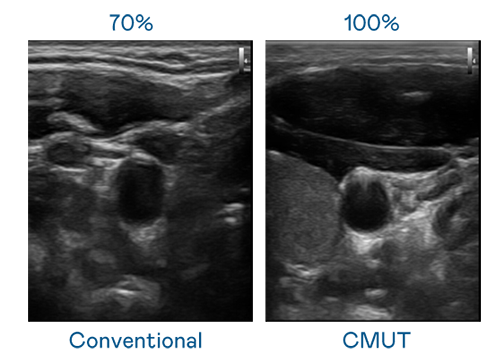

CMUT 技术是一种用电容式微机电元件来产生超音波讯号的技术。与传统 PZT 压电式技术相比,CMUT 频宽增加 30%,更宽频的超音波讯号让影像解析度大幅提升,是实现高影像品质医疗超音波扫描、促进精准医疗发展的关键技术。

大频宽带来超清晰影像

超音波影像的解析度高低,首先取决于探头能发出的讯号频宽。澳门威尼斯人 CMUT 可提供高清晰的超音波讯号,提供高频宽、高灵敏度、影像纹理细节更高的超音波影像,协助医护人员缩短影像判读时间及利用精准的医疗影像进行诊断。